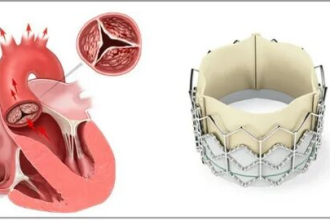

أمراض صمامات القلب تُشير إلى أي خلل يصيب صمامات القلب الأربعة (الميترالي، الأبهري، ثلاثي الشرفات، الرئوي)، والتي تُنظّم تدفق الدم داخل القلب وبين القلب وباقي الجسم. هذه الأمراض قد تؤدي إلى صعوبة في تدفق الدم بشكل طبيعي، مما يؤثر على وظيفة القلب وكفاءته.

- تضيق الصمامات: يحدث عندما تصبح الصمامات ضيقة، ما يُعيق تدفق الدم. مثال: تضيق الصمام الأبهري.

تعتمد العلاجات على نوع المرض وشدته، وتشمل الأدوية للتحكم في الأعراض أو تحسين وظائف القلب، والقسطرة لتوسيع الصمام الضيق، أو الجراحة لإصلاح أو استبدال الصمام المتضرر.

أفضل أنواع صمامات القلب أيهما تختار الطبيعي أم الصناعي؟

قد يصل بك الطريق أحياناً إلى طريق مسدود…

تتعدد الأمراض والمشاكل التي يمكن أن تصيب القلب،…

الصمام المعدني للقلب | مميزاته وعيوبه والمشاكل المصاحبة لتركيبه

الصمام المعدني للقلب، هو الخيار الثاني لمرضى صمامات…